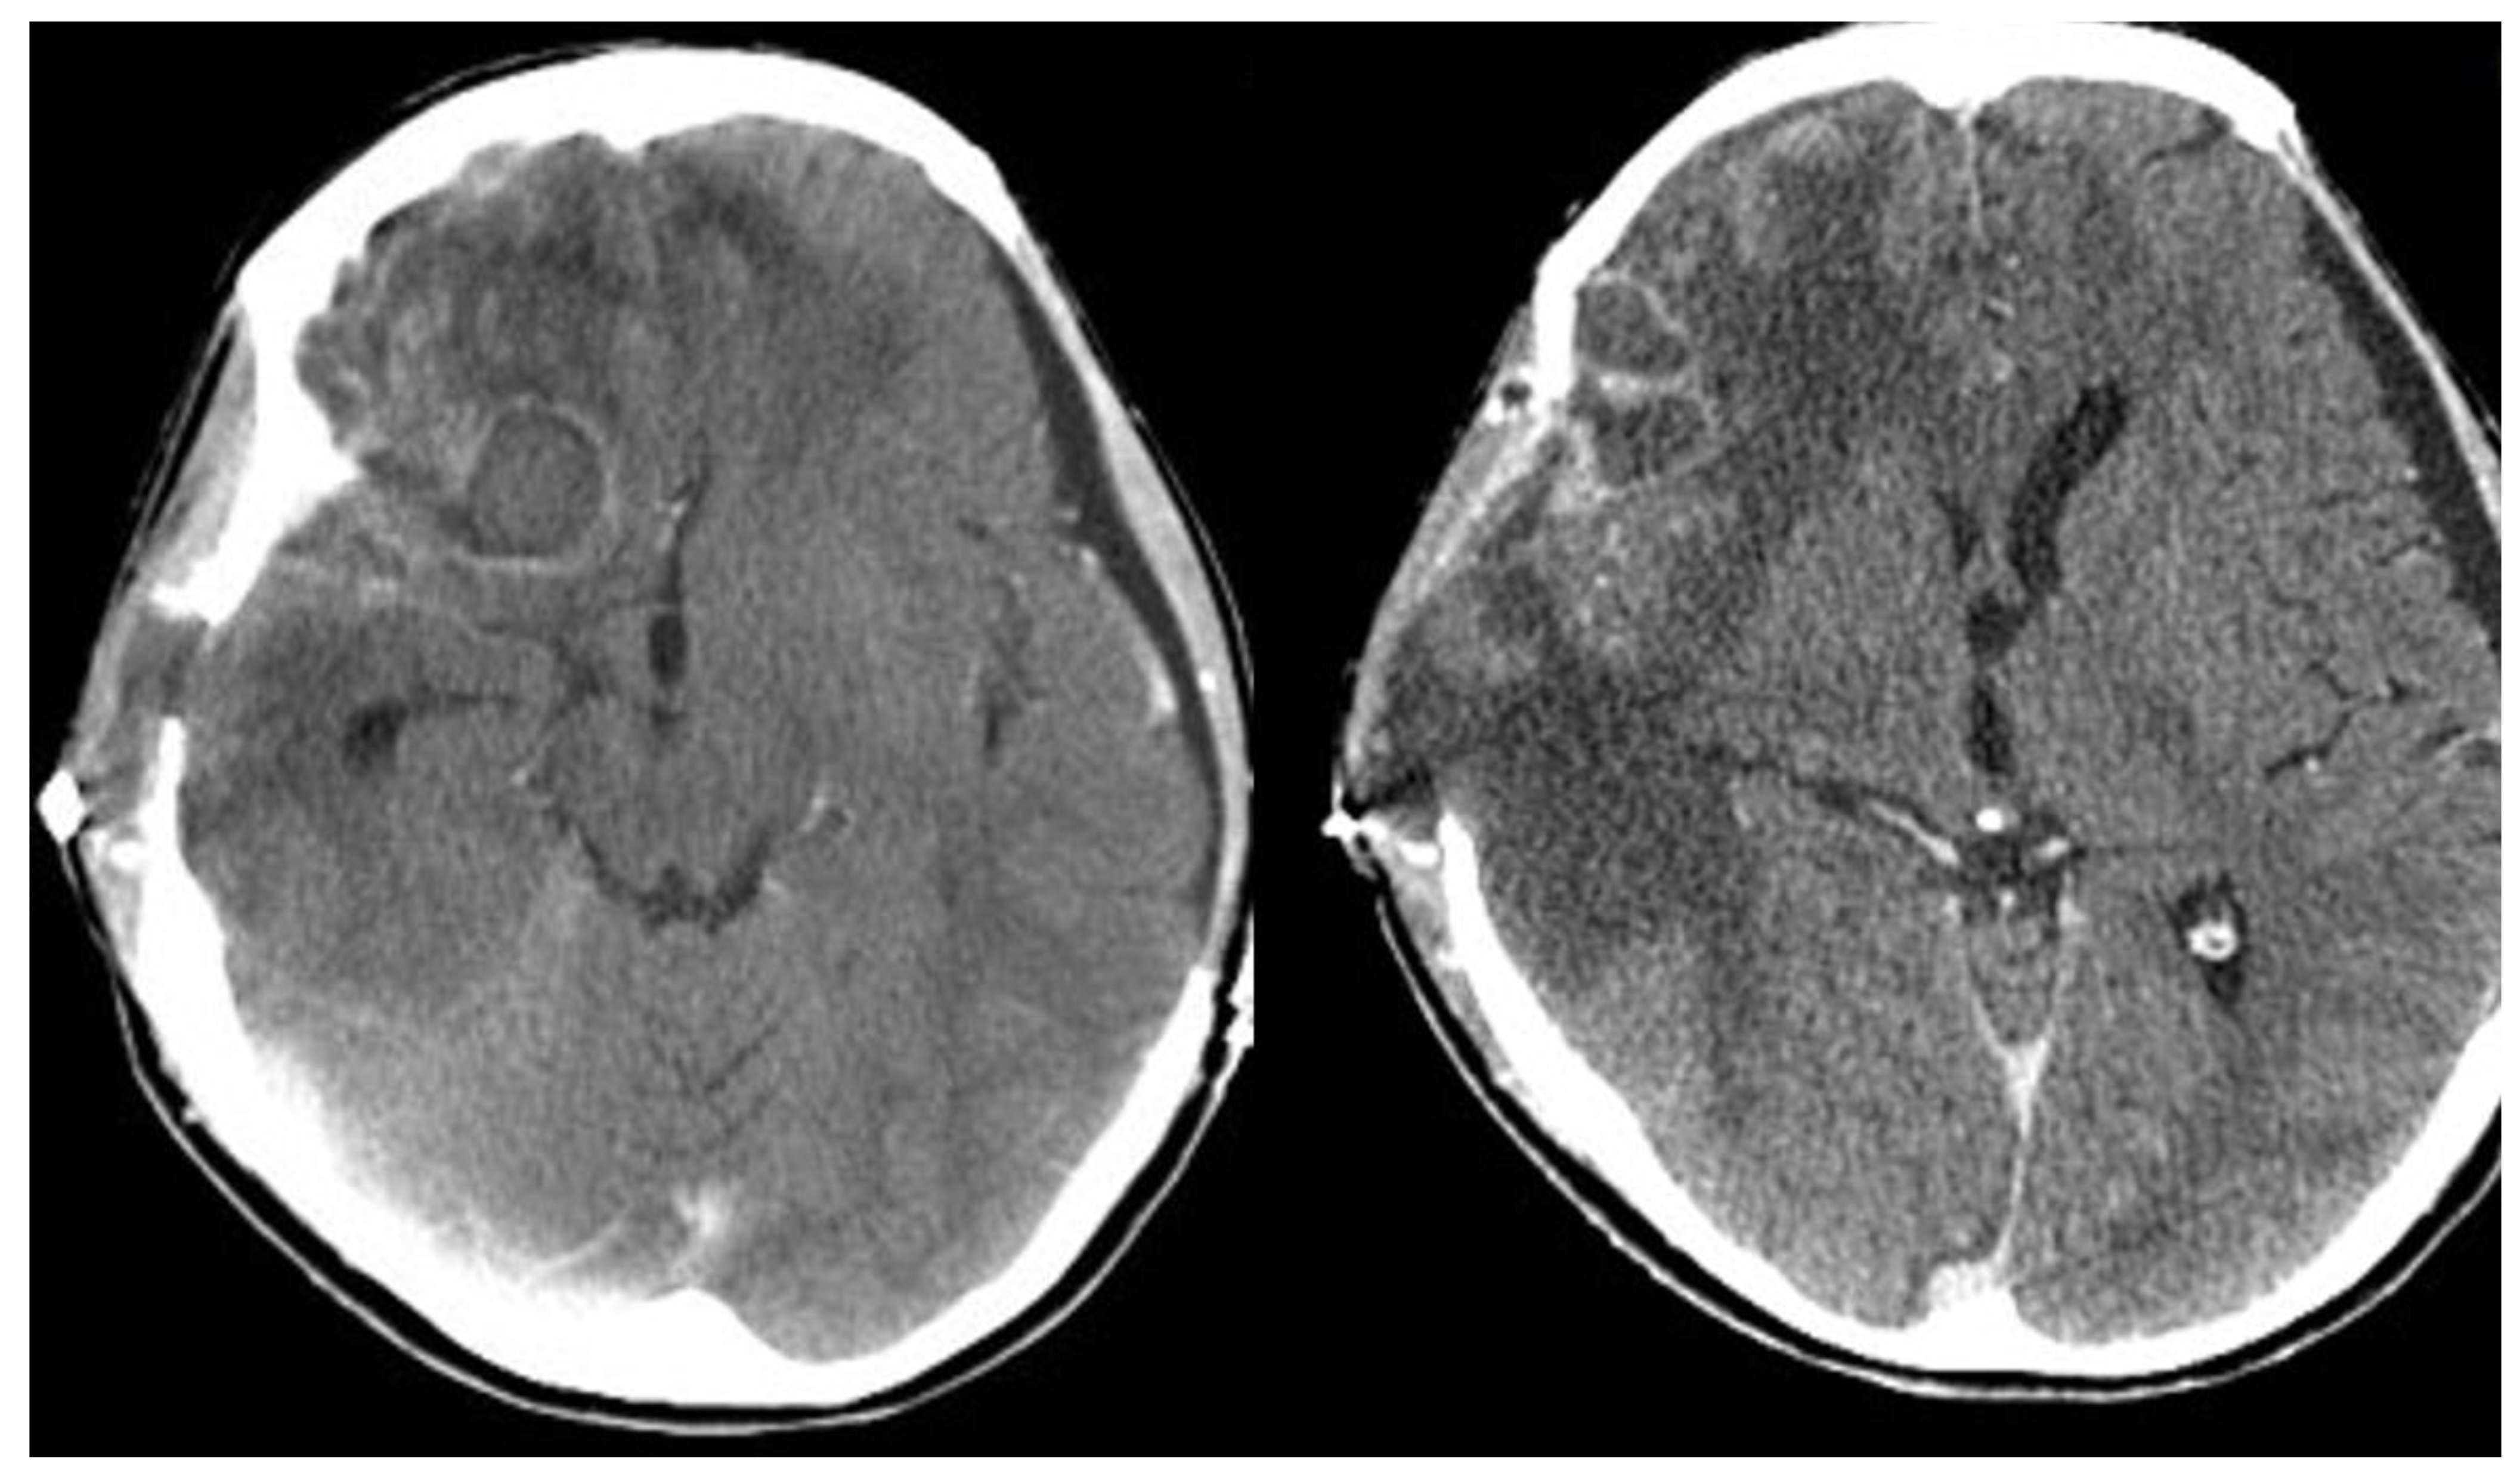

At that point, a new CT scan revealed parietal, temporal and frontal abscesses at the right side (Figure 2). The patient underwent surgery; surgical debridement was performed, while specimens were microscopically and histologically examined, as well as cultured. Direct microscopy with fluorescent dye (Blankophor P) again revealed the same findings, compatible with mucormycosis. Furthermore, hematoxylin–eosin stain, performed in tissue specimens, showed fungal elements similar to those with BlanKophor P (Figure 3). It is of note that cultures did not yield any fungal organism at this point, probably due to the treatment with liposomal amphotericin B. Magnetic resonance imaging (MRI) performed postoperatively, for the evaluation of the infection’s course, revealed enclosed collections absorbing contrast, indicating abscesses at the parietal, temporal and frontal lobe at the right side (Figure 4).

Isolated cerebral mucormycosis mainly occurs in young adults, while headache, fever, focal weakness and altered mental status represent the main symptoms. It is also of note that in most cases, the infection is localized in the basal ganglia [4,17,18]. The reported patient was also young. She had been intubated after she had been brought to the Emergency Department; hence, symptoms following the first surgical procedure and infection initiation were not evident. Nevertheless, the present case is quite different from those described so far in the literature, since the infection was due to direct inoculation, and there was no hematogenous spread. It must be noted that no other Lichtheimia infections had been diagnosed in the facility; hence, inoculation most probably occurred during the initial trauma and not during surgery, since the air filtration system in the operating room meets the highest standards. The infected sites in the reported patient were the right parietal, temporal and frontal lobe, as shown in the CT scan (Figure 2).

Regarding imaging techniques indicating diagnosis, the modality of choice is brain MRI with special sequences, including gradient echo and susceptibility weighting, to assess for microhemorrhage, indicating a potentially invasive process [16]. However, as shown in the reported case, contrast CT scanning may also be useful during the diagnostic process, revealing infectious regions [4,20].

Figure 2. Axial contrast-enhanced CT images following bilateral craniectomy performed 2 weeks ago. The exam displayed postoperative changes more evidently in the right cerebral hemisphere, where concurrent peripherally enhancing lesions were also demonstrated, primarily suspicious of representing abscesses.